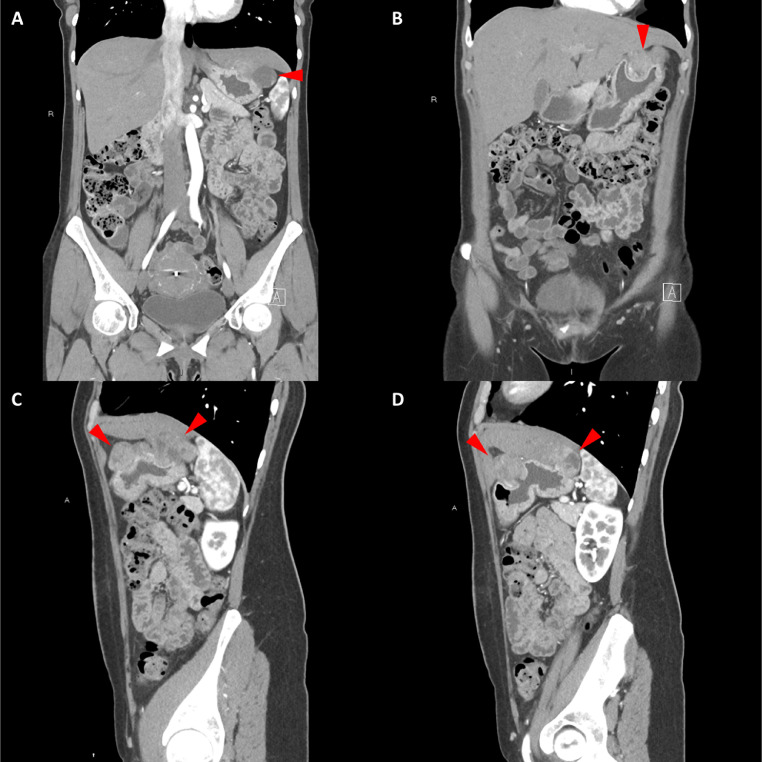

胸部、腹部和骨盆的对比增强动脉和静脉期 CT 显示多个圆形、主要是血管丰富的异质肿块,具有囊性和实性成分,起源于胃底和胃体(图 2-4)。 病变部分呈外生结构,被认为位于粘膜下层。 在颈部多发同步性副神经节瘤的情况下,最初的鉴别诊断包括多发性副神经节瘤、多发性 GIST 以及转移性疾病。